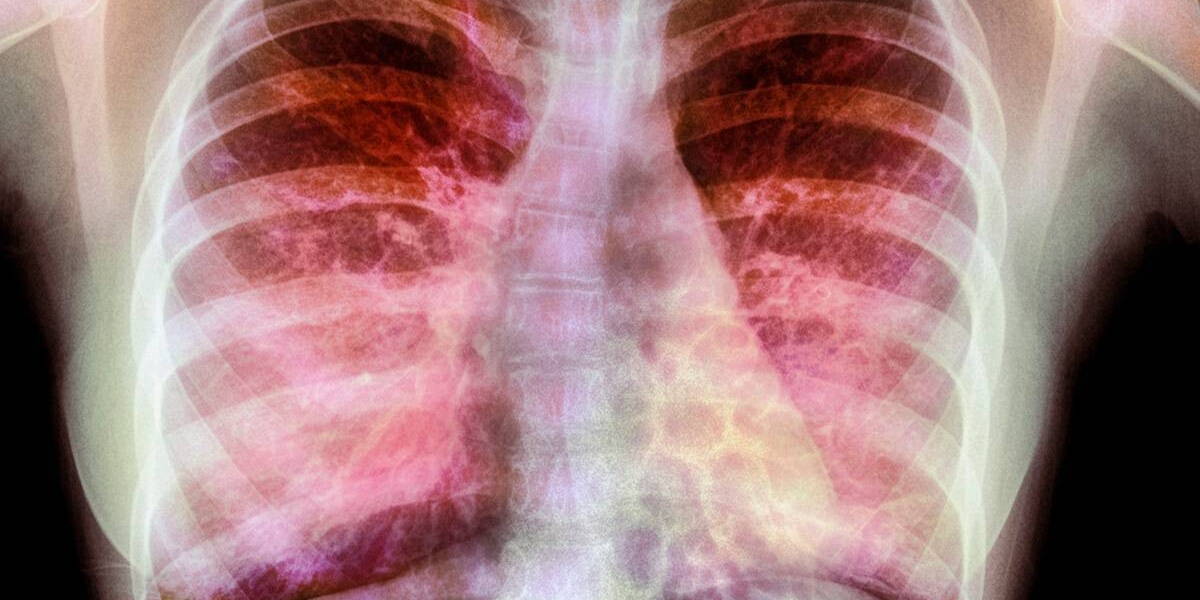

Ruim 40 Europese centra gaan de komende vijf jaar onder leiding van het UMC Utrecht onderzoek doen naar nieuwe behandelingen tegen taaislijmziekte, cystic fibrose. De Europese Commissie heeft hiervoor 6,7 miljoen euro subsidie toegekend. Het onderzoekstraject staat onder leiding van professor Kors van der Ent.

Onderzoek en subsidie zijn bedoeld om nieuwe, gepersonaliseerde behandelingen te realiseren voor Europese CF-patiënten. Nu krijgen veel CF-patiënten alleen symptoombestrijding. “In dit onderzoek willen we specifiekere groepen patiënten gaan behandelen, vooral patiënten die een zeldzaam genetisch profiel hebben”, licht Van der Ent toe. “Op die manier kunnen we gerichter op zoek gaan naar goede medicijnen en behandelingen voor hen.”